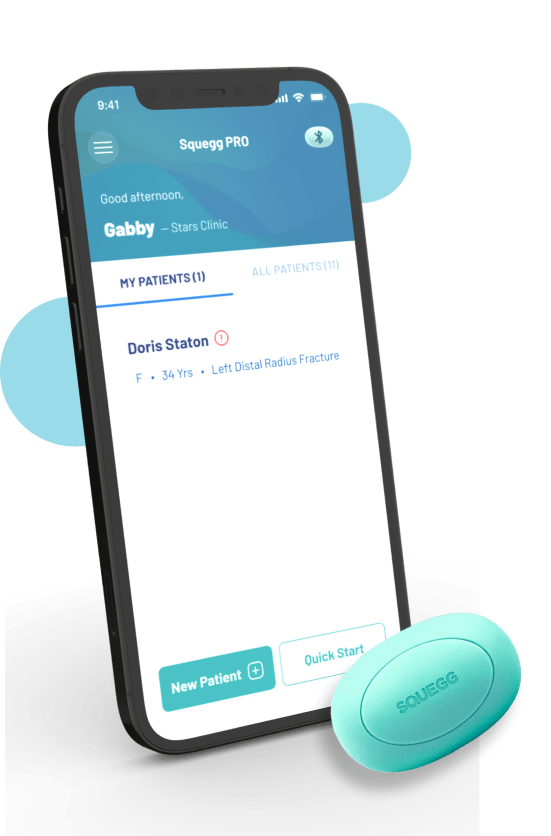

Squegg Ecosystem

Grip/ Pinch Assessment And Data Tracking

Portable And Convenient